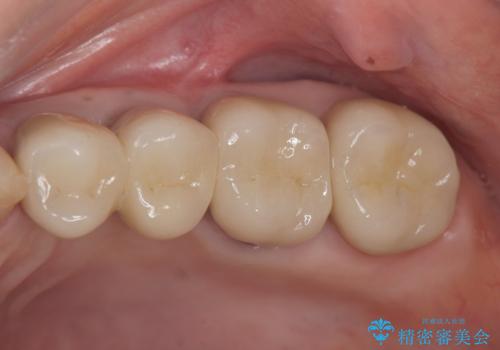

骨の造成を伴うインプラント治療

- 97.9万円(インプラント×2・アバットメント×2・仮歯×2・ジルコニアクラウン×2・骨造成)費用は治療当時の料金となります

インプラント治療を行うにはインプラント周囲に十分な骨の幅・高さが必要です。

今回はが原因で失われてしまった骨の幅を回復することで長期的な予後を見込めるインプラント治療を行うことができました。